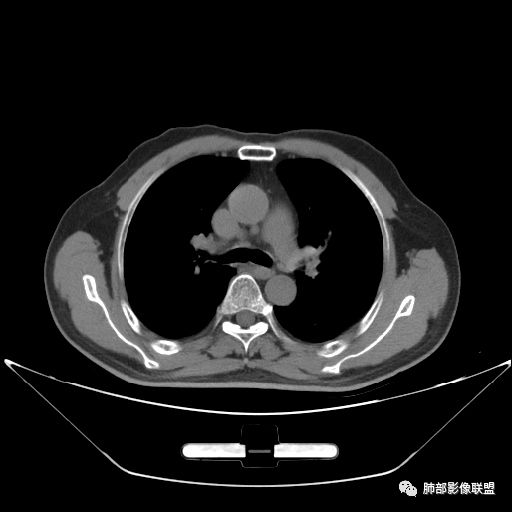

住院4天后行胸部增强CT

静脉期

吴婧老师和南边老师都对该病例进行了深入分析。从支气管管壁的增厚,支气管狭窄后扩张,支气管粘液栓,病灶形态,到病灶不均匀强化及坏死彻底,到周边病灶及肺组织空气的潴留,加之纵隔内淋巴结肿大伴钙化等等,都支持慢性炎性病灶,尤其是结核。

墨西哥仙人掌征---结核        影像上结核灶,粗大的均匀枝干,推测是支气管囊状扩张引起的,在非支气管区,形成圆形坏死囊群;如果这些坏死比较稀薄,又遇到扩张支气管,就会形成粗大的“墨西哥仙人掌”。结核引起的支气管近端炎症纤维化,可以造成支气管阻塞,从而将干酪样坏死物封堵在管腔内。仙人掌主干内部应该是干酪为主,稀薄的,具有流动性,时间久了会出现钙化。

结核坏死与鳞癌鉴别有一点是结核坏死没有方向性,鳞癌有。鳞癌靠近支气管近端部分,血供容易维持,不易坏死,所以坏死靠外侧。而结核干酪样坏死,把一定体积的流动性坏死物,包裹起来,什么形状最省料?坏死物包裹,表面积最省的自然是圆球形,而遇到支气管,坏死物一多,就把支气管撑大了。包裹物是就地取材,扩张的支气管就成了包裹结构。